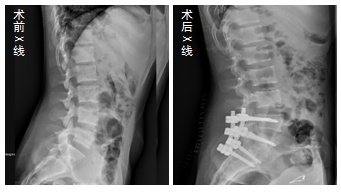

我院骨科于2018年10月26日收治了一名腰5骶1椎结核患者,患者为女性,23岁,农民,因“腰痛6月,发现左腰背部一痛性包块3个月”入院。在我院骨科医生积极救治下,经四川省人民医院专家远程会诊,通过医院领导统筹协调,我院邀请了西南医科大学附属医院雷飞教授于11月24日指导我院骨科医生成功经脊柱后路实施了腰4-骶1椎体钉棒系统内固定、腰5骶1椎体结核病灶清除、自体髂骨植骨融合术、腰部结核病灶清除术。

脊柱后路手术创伤小、出血少,患者术后恢复快,患者满意度高,目前患者即将康复出院。此例患者的成功救治是我院紧跟目前脊柱手术发展步伐的重要里程碑,填补了我院对下腰椎后路结核病治疗的空白,为我州及邻近各县广大患者带来了福音。